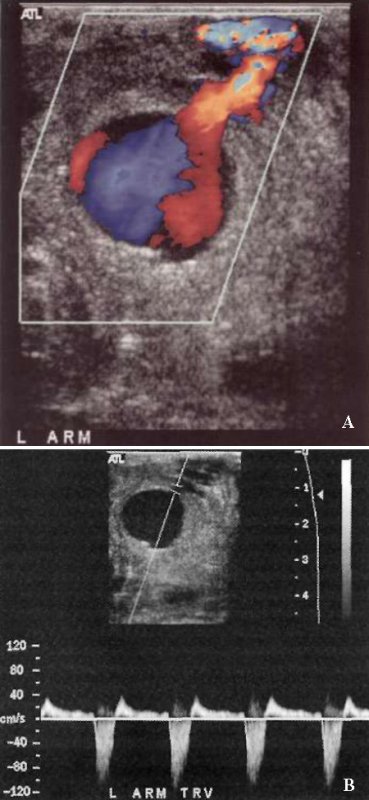

Наиболее частой локализацией ложной аневризмы является общая бедренная артерия, поверхностная бедренная артерия, подколенная, лучевая, почечная и селезеночная артерии. Кроме этого, ложные аневризмы могут формироваться вокруг искусственных сосудов – шунтов (фото 2).

УЗИ: Ложная аневризма артериовенозной диализной фистулы

Фото 2. Ложная аневризма артериовенозной диализной фистулы. А – цветовая допплерограмма демонстрирует ложную аневризму, которая исходит из артериовенозной диализной фистулы. В – спектральная допплерограмма демонстрирует кровоток внутрь и наружу из аневризмы характерной двухфазной формы с полным обратным током в диастолу